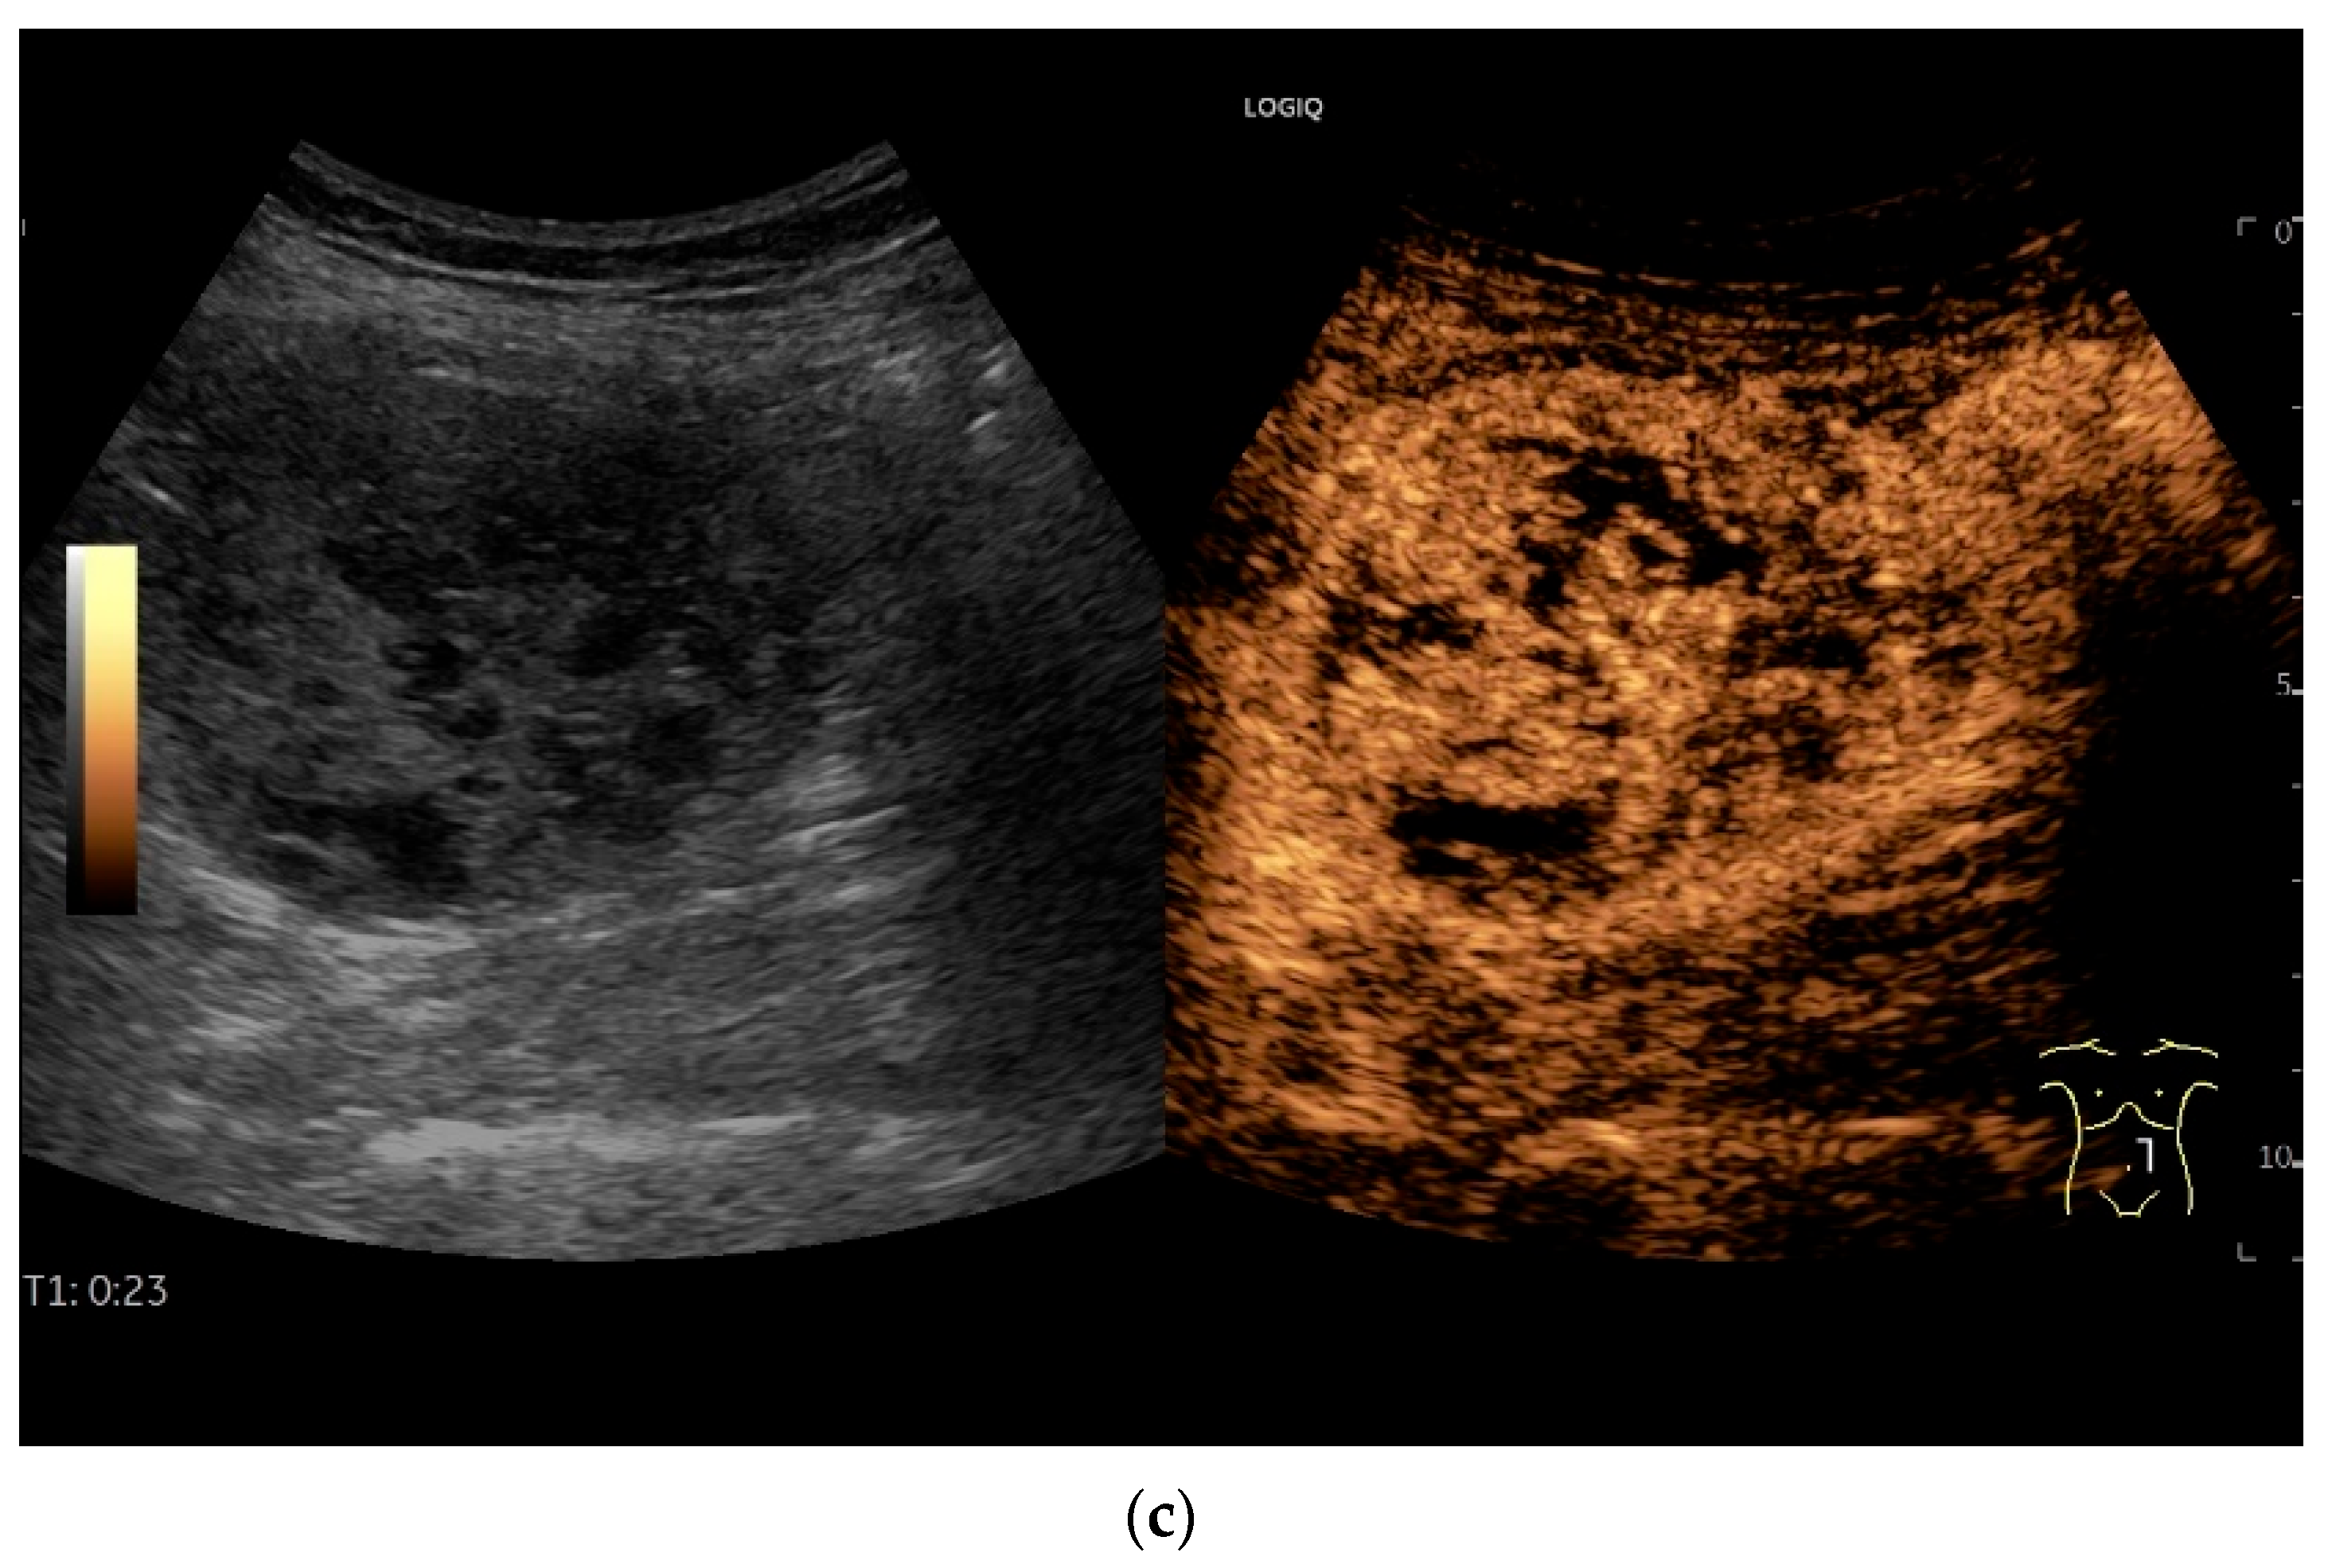

- Schwarze, V.; Marschner, C.; Grosu, S.; Rübenthaler, J.; Knösel, T.; Clevert, D.A. Modern sonographic imaging of abdominal neuroendocrine tumors. Radiologe 2019, 59, 1002–1009. [Google Scholar] [CrossRef] [PubMed]

- Zhao, J.Y.; Zhuang, H.; Luo, Y.; Su, M.G.; Xiong, M.L.; Wu, Y.T. Double contrast-enhanced ultrasonography of a small intestinal neuroendocrine tumor: A case report of a recommendable imaging modality. Precis. Clin. Med. 2020, 3, 147–152. [Google Scholar] [CrossRef]

| Neuroendocrine tumor | Small, nodular hypoechoic wall thickenings, mostly in the submucosa with spreading into the other layers. Usually with small vessels on CDI. Regionally enlarged lymph nodes. Multilocular manifestations are possible. |